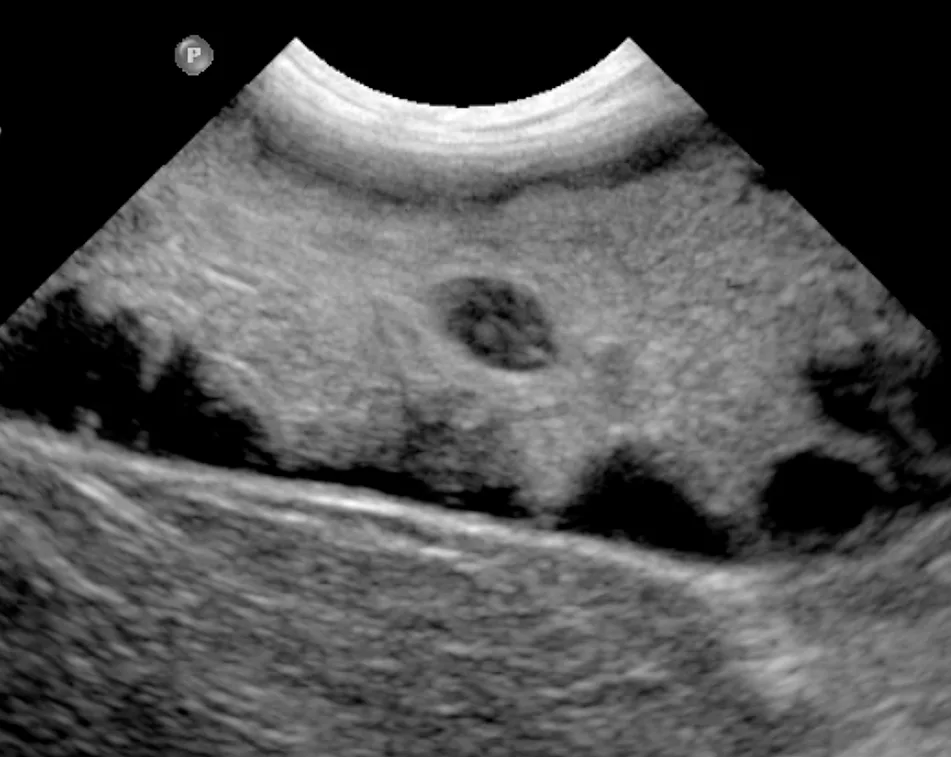

Ultrasonographic image of a GBM showing the classic kiwi-like appearance

Abdominal ultrasonography is key to diagnosis of GBMs. The classic description of GBMs is a kiwi-like appearance of intraluminal gallbladder contents with hyperechoic immobile striations of inspissated bile in hypoechoic mucus structures (Figure 1). Other ultrasonographic appearances of GBMs include echogenic immobile biliary sludge filling the gallbladder or a stellate pattern (Figure 2).6,10,11 These different GBM appearances on ultrasonographic images likely represent a continuum of early to mature mucoceles.6 Ultrasonography cannot be used alone to determine the clinical significance of GBMs or guide treatment decisions unless there is clear evidence of biliary rupture or obstruction that warrants urgent surgical intervention (see Gallbladder Rupture).1,3,10